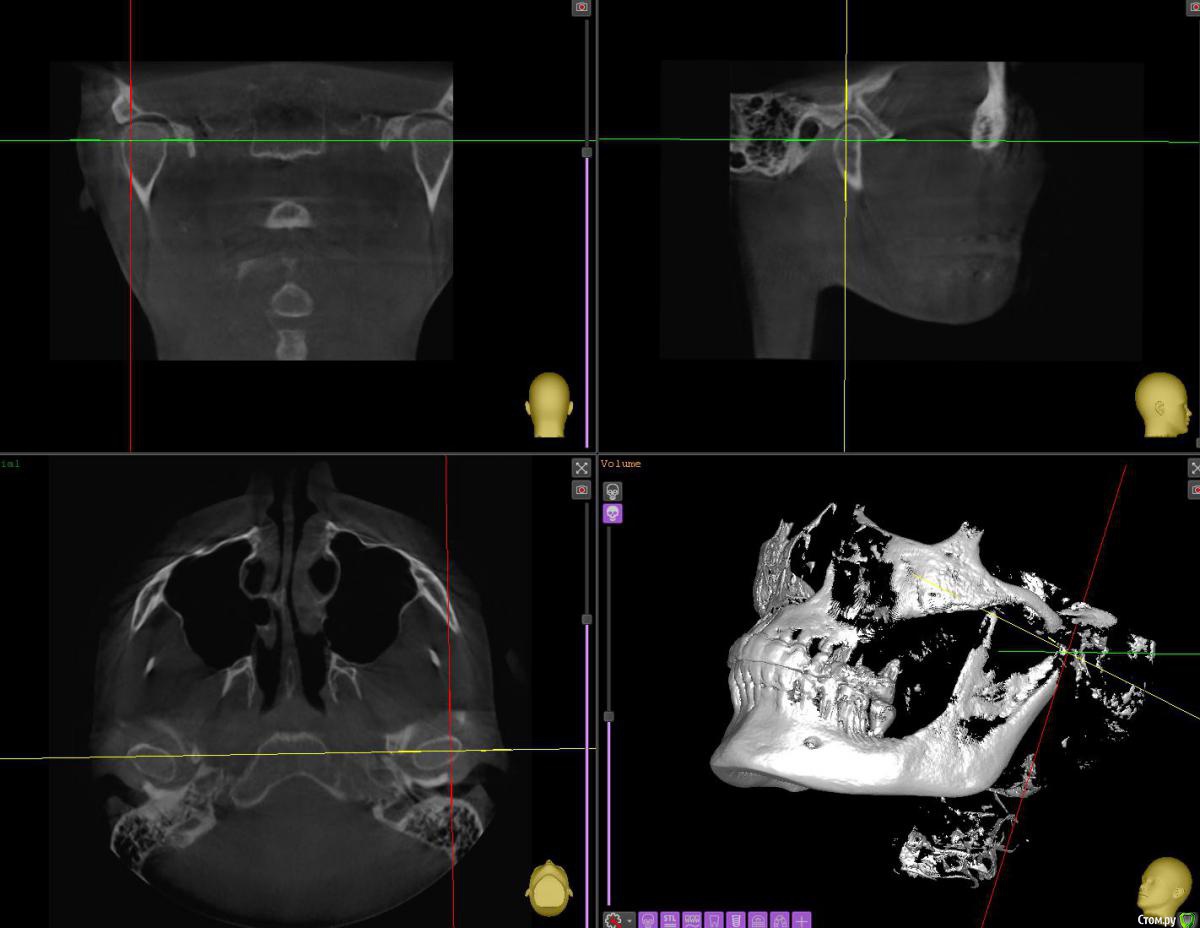

АнтонТЛТ Опубликовано 29 июня, 2020 Поделиться Опубликовано 29 июня, 2020 Срезы надо иначе выставлять, крутануть перекрестие. Примерно чтобы вот так получилось. Ссылка на комментарий

АнтонТЛТ Опубликовано 29 июня, 2020 Поделиться Опубликовано 29 июня, 2020 Вот так короче) 1 Ссылка на комментарий